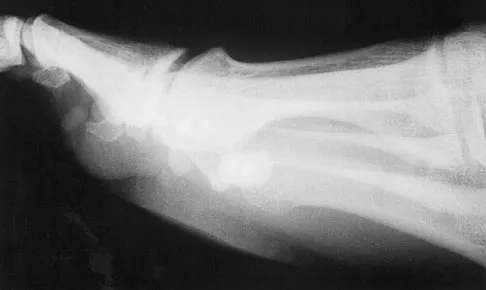

A 20-year-old woman sustained the closed injury shown in Figures 49a and 49b in a motor vehicle accident. Examination reveals that this is an isolated injury; however, she has a complete radial nerve palsy. Management should consist of

Explanation

Lacerated radial nerves are associated with open humeral fractures. All open humeral fractures with radial nerve palsy should be managed with radial nerve exploration and skeletal stabilization. Closed humeral fractures with associated radial nerve palsy usually have an intact nerve with neurapraxia. Most of these patients recover without surgical treatment. If the patient has multiple injuries, skeletal stabilization may be indicated to improve mobilization. For an isolated closed humeral fracture with a radial nerve palsy, the treatment of choice is splinting for 1 to 2 weeks, followed by a humeral fracture brace. Ring D, Chin K, Jupiter JB: Radial nerve palsy associated with high-energy humeral shaft fractures. J Hand Surg Am 2004;29:144-147.